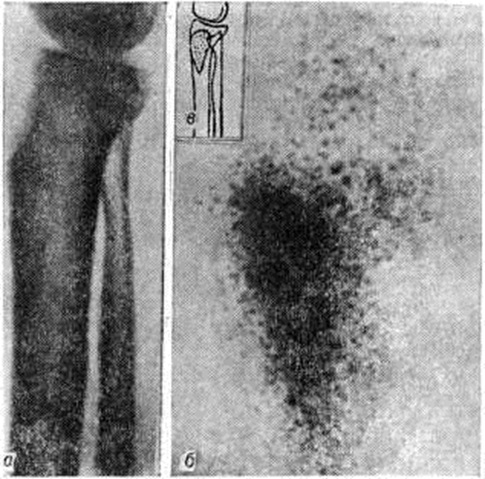

Определённую роль, особенно в дифференциальной диагностике хронический Остеомиелит и опухоли кости, начинает играть радиол, метод исследования. Сцинтиграфия (смотри полный свод знаний) после введения изотопов (пирофосфата технеция или стронция) помогает установить первоначальные признаки воспалительного процесса и распространённость его в различных костях раньше, чем рентгенография (рисунок 18), однако мелкие секвестры и остеомиелитические очаги легче обнаружить с помощью рентгенологическое метода.

При лабораторный исследовании крови в фазе ремиссии обнаруживается умеренно выраженная анемия и лейкоцитоз со сдвигом формулы влево при заметном ускорении РОЭ. Количество общего белка крови, как правило, находится в пределах средних цифр нормы, но наблюдается диспротеинемия: гипоальбуминемия, гиперглобулинемия (главным образом за счёт гамма-глобулиновой фракции) и снижение белкового коэффициента. В фазе обострения возникают изменения, типичные для вспышки гнойного процесса: нарастают гипохромная анемия, лейкоцитоз, нейтрофилез, ускоряется РОЭ, диспротеинемия становится более выраженной.